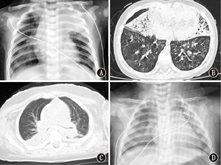

双肺受累8例(47.1%),单侧肺受累5例(29.4%);斑片影7例(41.2%),实变影6例(35.3%),双肺纹理粗重模糊4例(23.5%),胸腔积液1例(5.9%),见图1。

注:A:4个月男婴,胸片可见双肺模糊斑片影,左肺上叶大片实变影;B:2岁5个月男童,胸部CT可见双肺野散在片影,右中叶及左舌段见实变影,容积略缩小,内见支气管充气怔;C:6个月男婴,胸部CT可见双肺野背侧片影及肺段实变影;D:8个月女婴,胸片见双肺内渗出增加,右肺内带模糊斑片影

A: a 4 months male infant,chest X-ray showed both lungs had patchy shadows,and the upper lobe of the left lung had consolidation; B: a 2 years and 5 months old male child,chest CT showed both lungs had scattered shadows,and right middle lobe and left lingular segment had consolidation,whose volume slightly narrowed and air bronchogram was positive; C: a 6 months male infant,chest CT showed the dorsal segment of both lungs had patchy shadows and consolidations; D: a 8 months female infant,chest X-ray showed both lungs had exudation,and right lung had patchy shadows